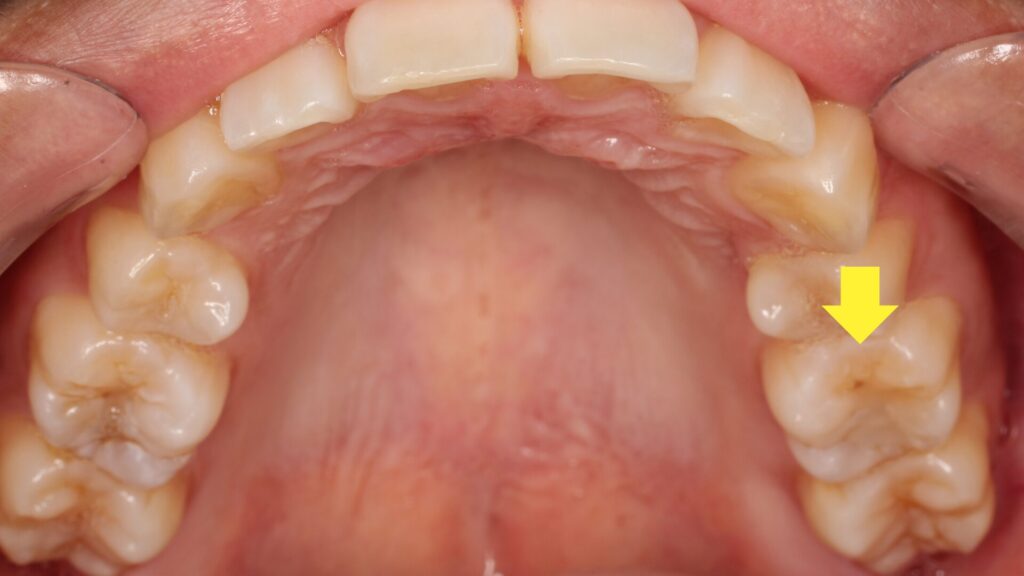

この歯ですが表面的には異常はありません。

しかし怪しい影の原因になっているのは明らかなので、古いプラスチックの詰め物を取ることに。

すると内部にはレントゲンにも映らないように慢性の虫歯が残っていました。

定期健診のレントゲン検査で見つかったものの原因はこれだったのです。

さらに精査すると歯の神経も半分は生きていたのですが、残り半分は既に死んでおり腐った状態でした。